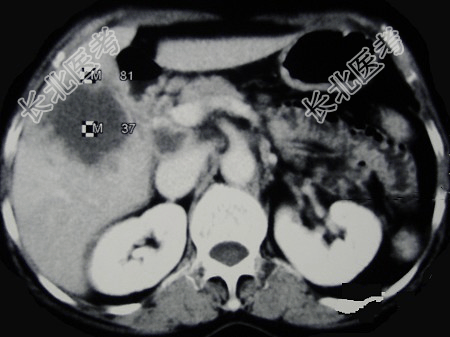

- 单项选择题女,65岁, 右季肋区疼痛二个月,CT扫描所见如图, 最可能的诊断为( )